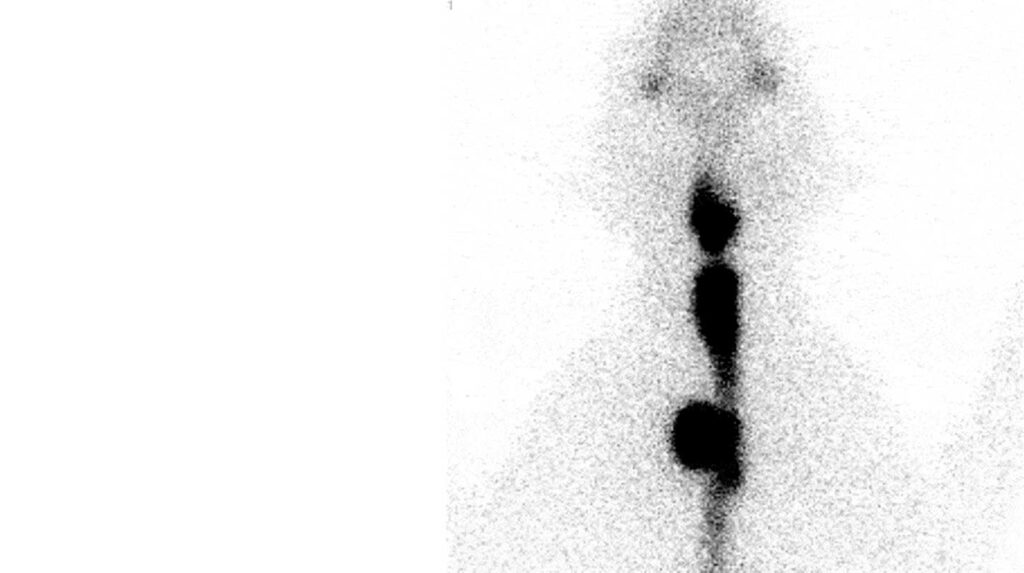

Er gibt es mehrere Behandlungsmöglichkeiten: Lebenslanges Medikamenten, Operationen, Futter oder eine Behandlung mit radioaktiven Jod 131. Für die Behandlung einer Hyperthyreose mit radioaktiven Jod 131 ist es wichtig zu wissen, ob eine Schilddrüse wirklich zu schnell arbeitet und wo das Gewebe sich befindet. Durch die Injektion einer radioaktiven Substanz (Technetium) wird sichtbar gemacht , wo es aktives Gewebe gebt.